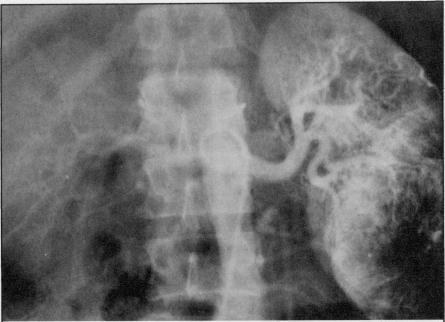

Although metastases to bones from solid tumors are very common, involvement of small bones of the hands and feet is extremely rare. One half of the cases reported in literature resulted from a primary tumor in the lung. Four cases seen over the last four years with metastases to bones of the hand and one case with metastases to foot bones are discussed. None of these patients had a lung primary tumor. Three of the four patients who had metastases to hand bones had the disease on the right side.

尽管实体瘤骨转移很常见,但手足小骨受累极为罕见。文献报道的病例中有一半源于原发性肺癌。本文讨论了过去四年中见到的4例手部骨转移病例和1例足部骨转移病例。这些患者均无原发性肺癌。4例手部骨转移患者中有3例病变位于右侧。